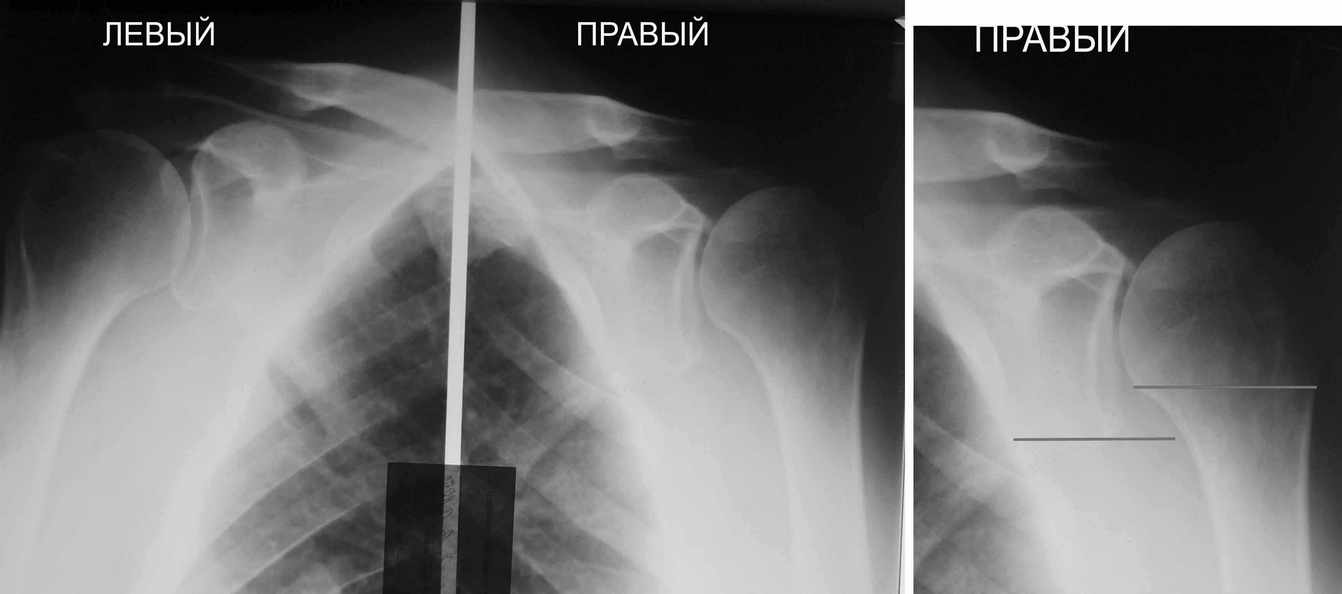

Физический активный мужчина 50 лет в мае 2009 года был оперирован на правом плечевом суставе. Выполнялся открытый шов надостной мышцы и субакромиальная декомпрессия по поводу ее частичного разрыва и импиджмент синдрома III степени.

В последующем, несмотря на активные занатия ЛФК, сформировалась приводяще-внутриротационная контрактура оперированного сустава (отведение до 80 градусов, наружная ротация до 15 градусов. Болевого синдрома нет, при пассивном отведении плеча создается впечатление "механического" препятствия движению.

На контрольных рентгенограммах складывается впечатление о сформировавшемсся верхнем подвивихе головки правой плечевой кости, как о причине контрактуры.